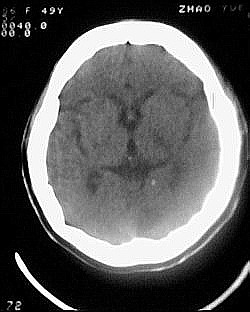

患者/49y/ 女/4年前有脑梗, 现因右侧肢体无力来院做ct扫描 ! 老师们看看这骨头有事吗?钙化点是什么原因呀??

2.双侧基底节区域多发性梗塞灶。

1、多发腔隙性脑梗塞是肯定的了。

1.双侧基底节区腔梗。

2.颅骨内外板广泛性增厚,板障狭窄甚至消失,双侧对称。无明显相应临床症状。考虑“泛发性骨皮质增厚症”。可进一步检查下颌骨及管状骨骨干。(下颌骨骨小梁增多、密集,密度增高亦为本病特点,管状骨骨干皮质向内增厚引起骨皮质厚度增加,骨密度增浓、髓腔狭窄但不消失,骨干周径较少增加)。与石骨症鉴别,后者很少影响颅盖骨和下颌骨,管状骨改变主要累及干骺端和骨骺,而骨干皮质较少增厚,椎体和髂骨翼有特征性表现。

“泛发性骨皮质增厚症,又称骨内膜增生症(endosteal hyperostosis):分为常染色体隐性遗传性疾病(van buchem)和常染色体显性遗传性骨硬化症(worth病)。后者更少见,亦较轻。两者的病理上均为骨内膜 成熟的板状新生骨形成,髓腔变窄。颅骨、颅底骨 、下颌骨,肋骨、四肢骨及骨盆骨、脊柱均可见骨内膜增生,髓腔变窄或消失,但骨外径不加大,骨骺不累及。”

本例的确应该这个病。建议楼主检查病人其他部位有无类似表现,以便确诊。